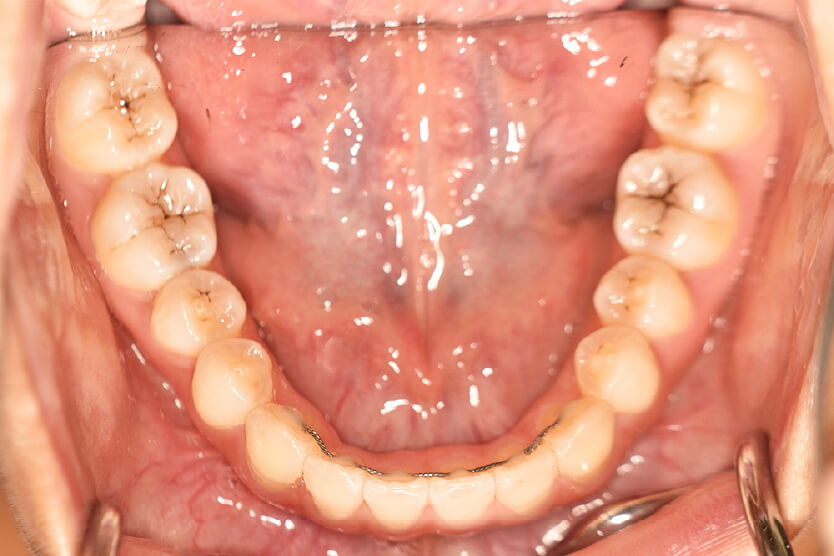

| 治療内容の詳細 | 初診時12歳の女性で、上顎前歯部の反対咬合を気にされ来院されました。 検査の結果、下顎前突、上顎前歯部叢生および上顎側切歯反対咬合を伴うアングルⅢ級不正咬合と診断しました。 治療としては、リンガルアーチを使用して、上顎側切歯を前方へ移動させ、反対咬合の改善を行い、マウスピース型矯正装置(インビザライン)で配列を行いました。 治療期間は1年5か月でした。 |